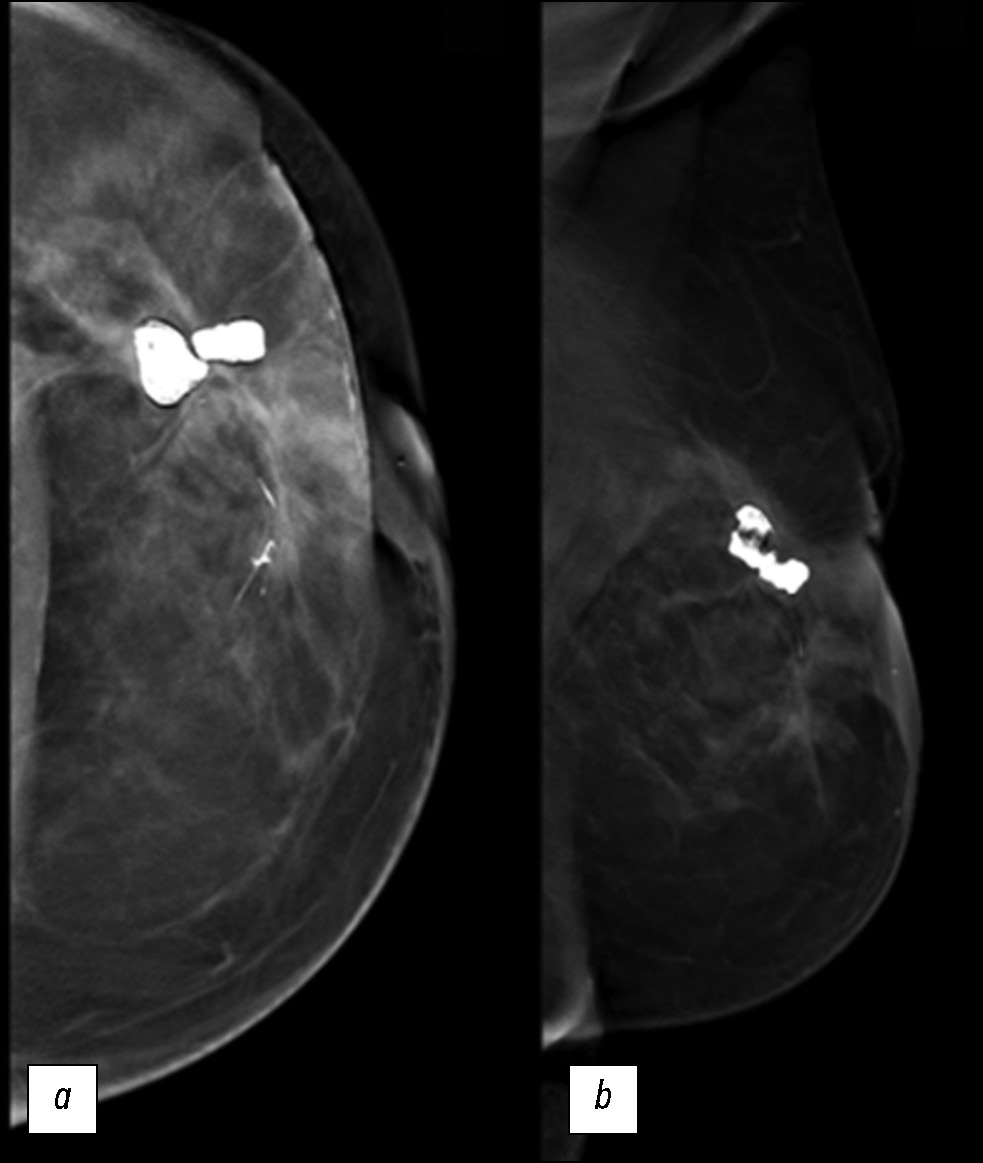

继发性乳腺血管肉瘤的特征:临床病例

摘要

本文描述了一个罕见的继发性乳腺血管肉瘤病例,患者是一名72岁的女性,患者是一名有乳腺癌病史的 72 岁女性。曾患乳腺癌。患者因左乳房外上象限无痛性可触及硬块来我院就诊,接受了全面的诊断检查,包括乳腺科、病理科和肿瘤科的会诊。在乳房造影、超声检查和磁共振成像等仪器诊断方法的帮助下,成功评估肿瘤的扩散程度、淋巴结损伤情况,以及是否存在远处转移。 组织活检结果证实了诊断。本文分析这一罕见病例的主要目的是教育性的,包括描述该疾病的临床表现和复杂诊断,以及讨论鉴别诊断和治疗策略。继发性乳腺血管肉瘤是一种罕见的侵袭性肿瘤,了解其独特之处对于做出正确的临床决策和改善患者的预后至关重要。由于发现较晚、硬块远处转移的风险增加以及治疗方案有限,该肿瘤的预后较差。在这种情况下,需要密切监测、采取积极的治疗策略和姑息治疗。